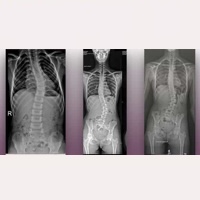

Sesje online dla pacjentów: Syndrom Arnolda Chiari I, Siringomielia idiopatyczna, Skolioza idiopatyczna i inne powiązane patologie. Czytaj więcej » 13 października, 2025